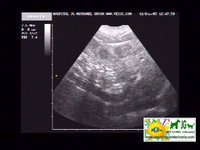

ecografía donde se aprecian las neoplasias hepáticas |